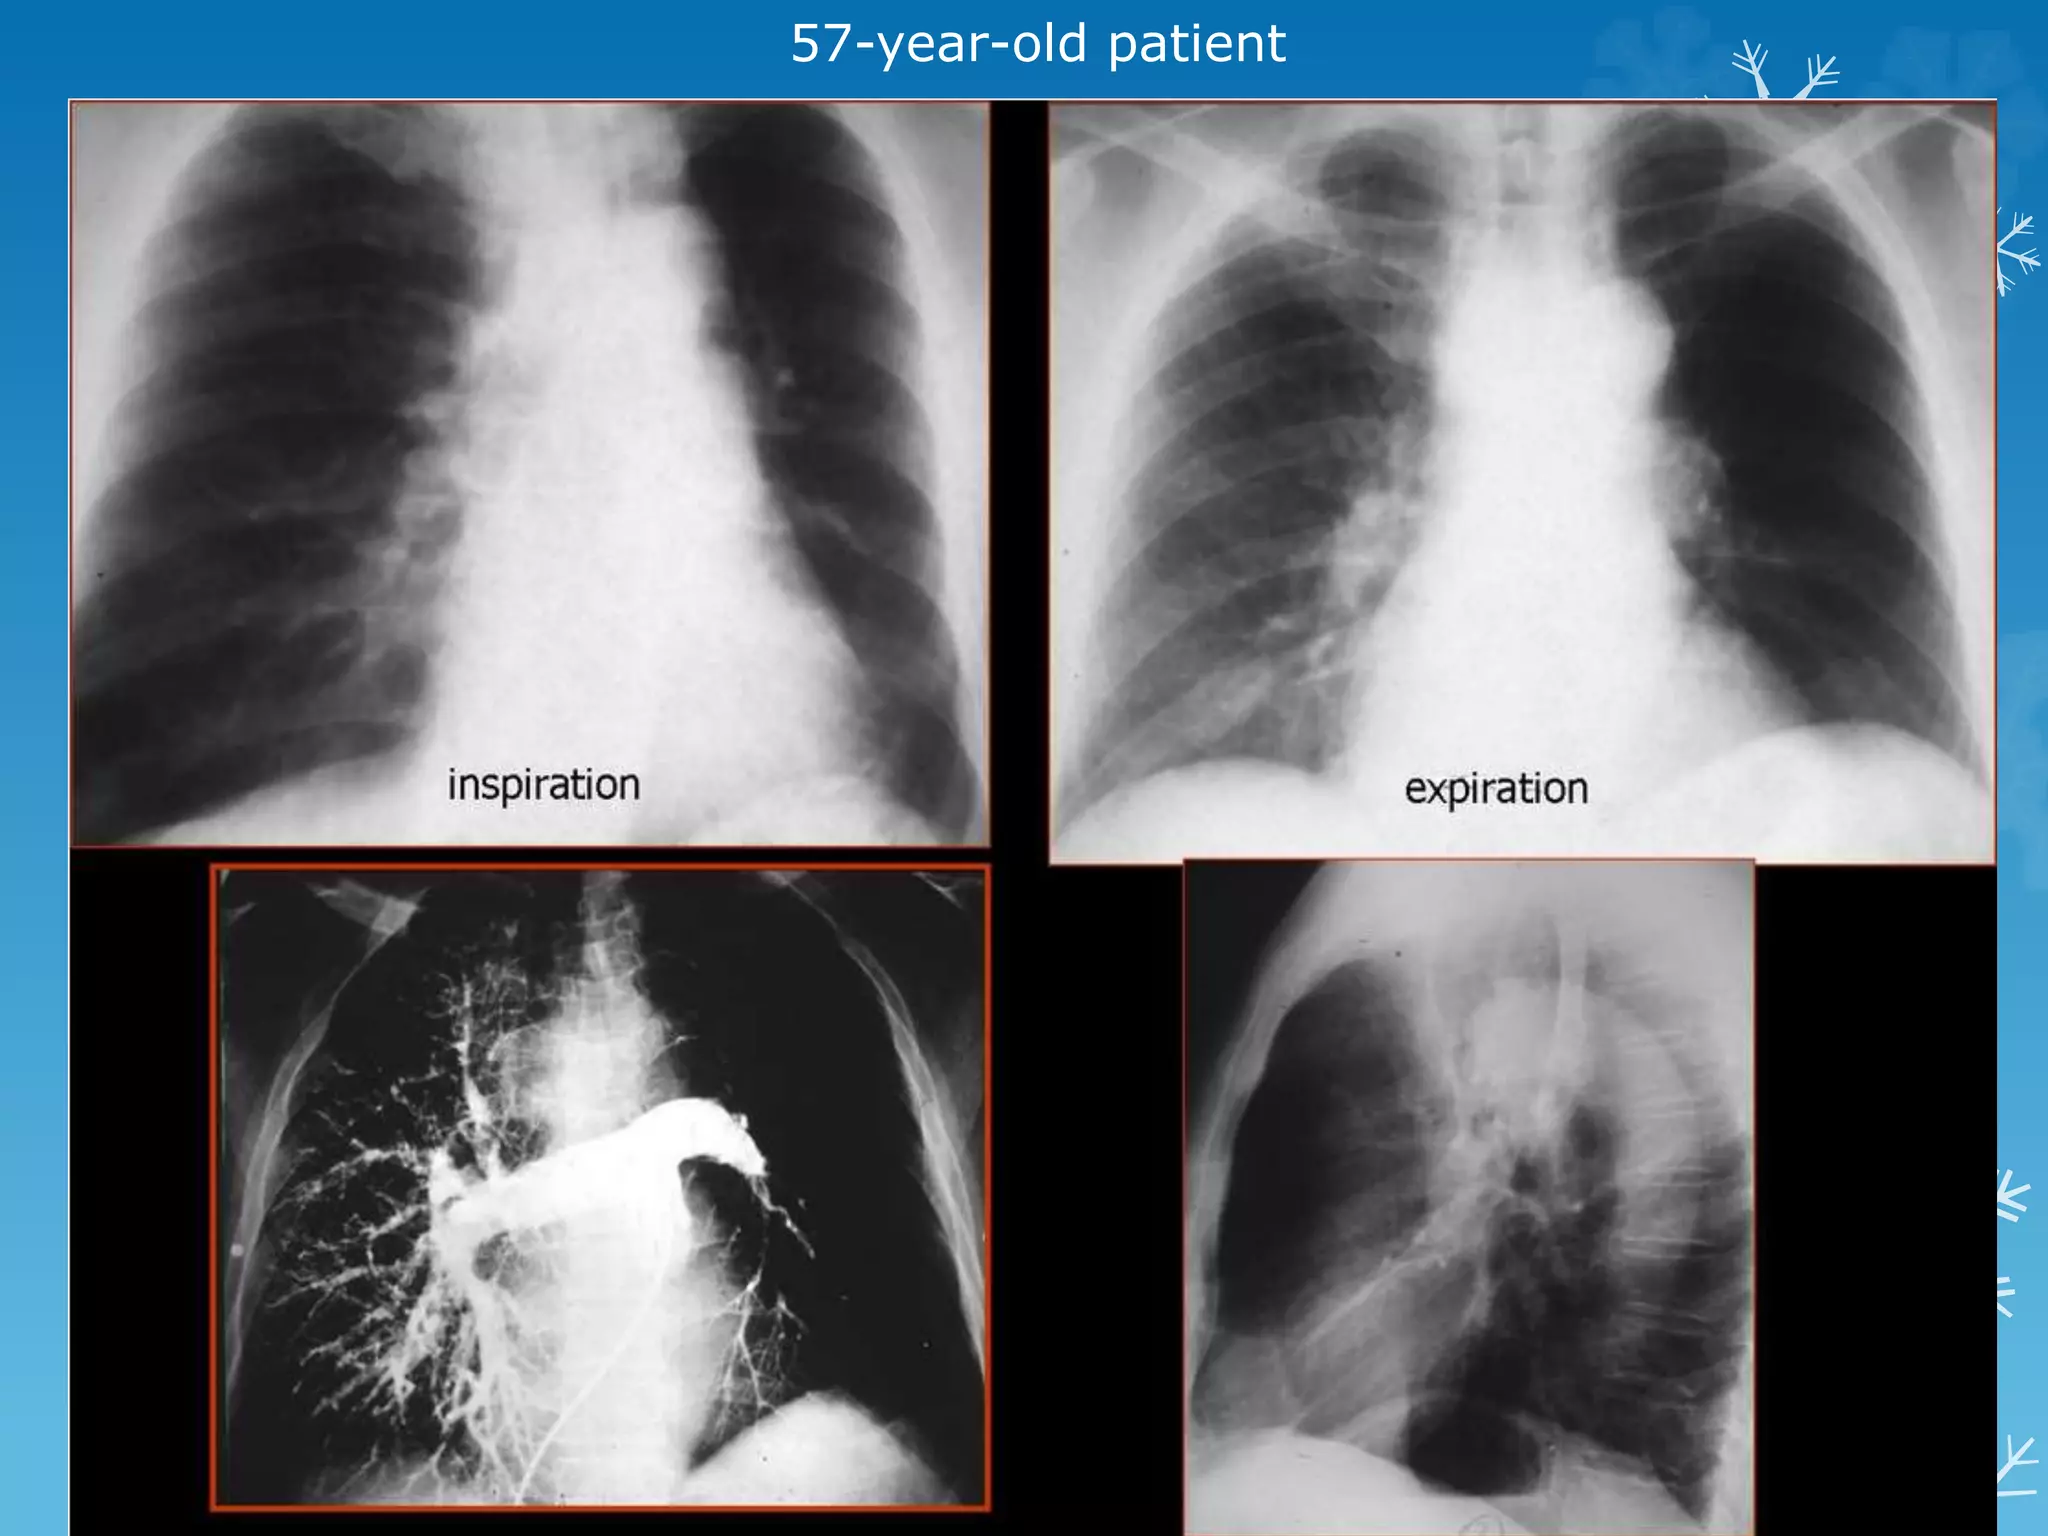

57-year-old patient